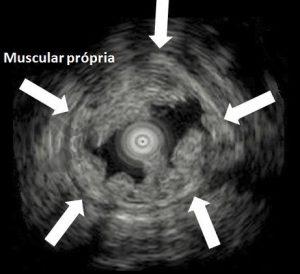

El secreto reside en un fenómeno denominado reducción gravitacional. Al llenar el colon con agua en lugar de aire, la flotabilidad provoca que la lesión se desplace lejos de la capa muscular propia, lo que permite que el asa capture suficiente tejido submucoso sin riesgo de afectación muscular ni perforación.

Figura 1: Ecoendoscopia que muestra la mucosa y la submucosa “flotando” mientras la capa muscular permanece estable. En UEMR las lesiones flotan en el agua debido a la reducción gravitacional, lo que permite una resección segura sin afectar la capa muscular.